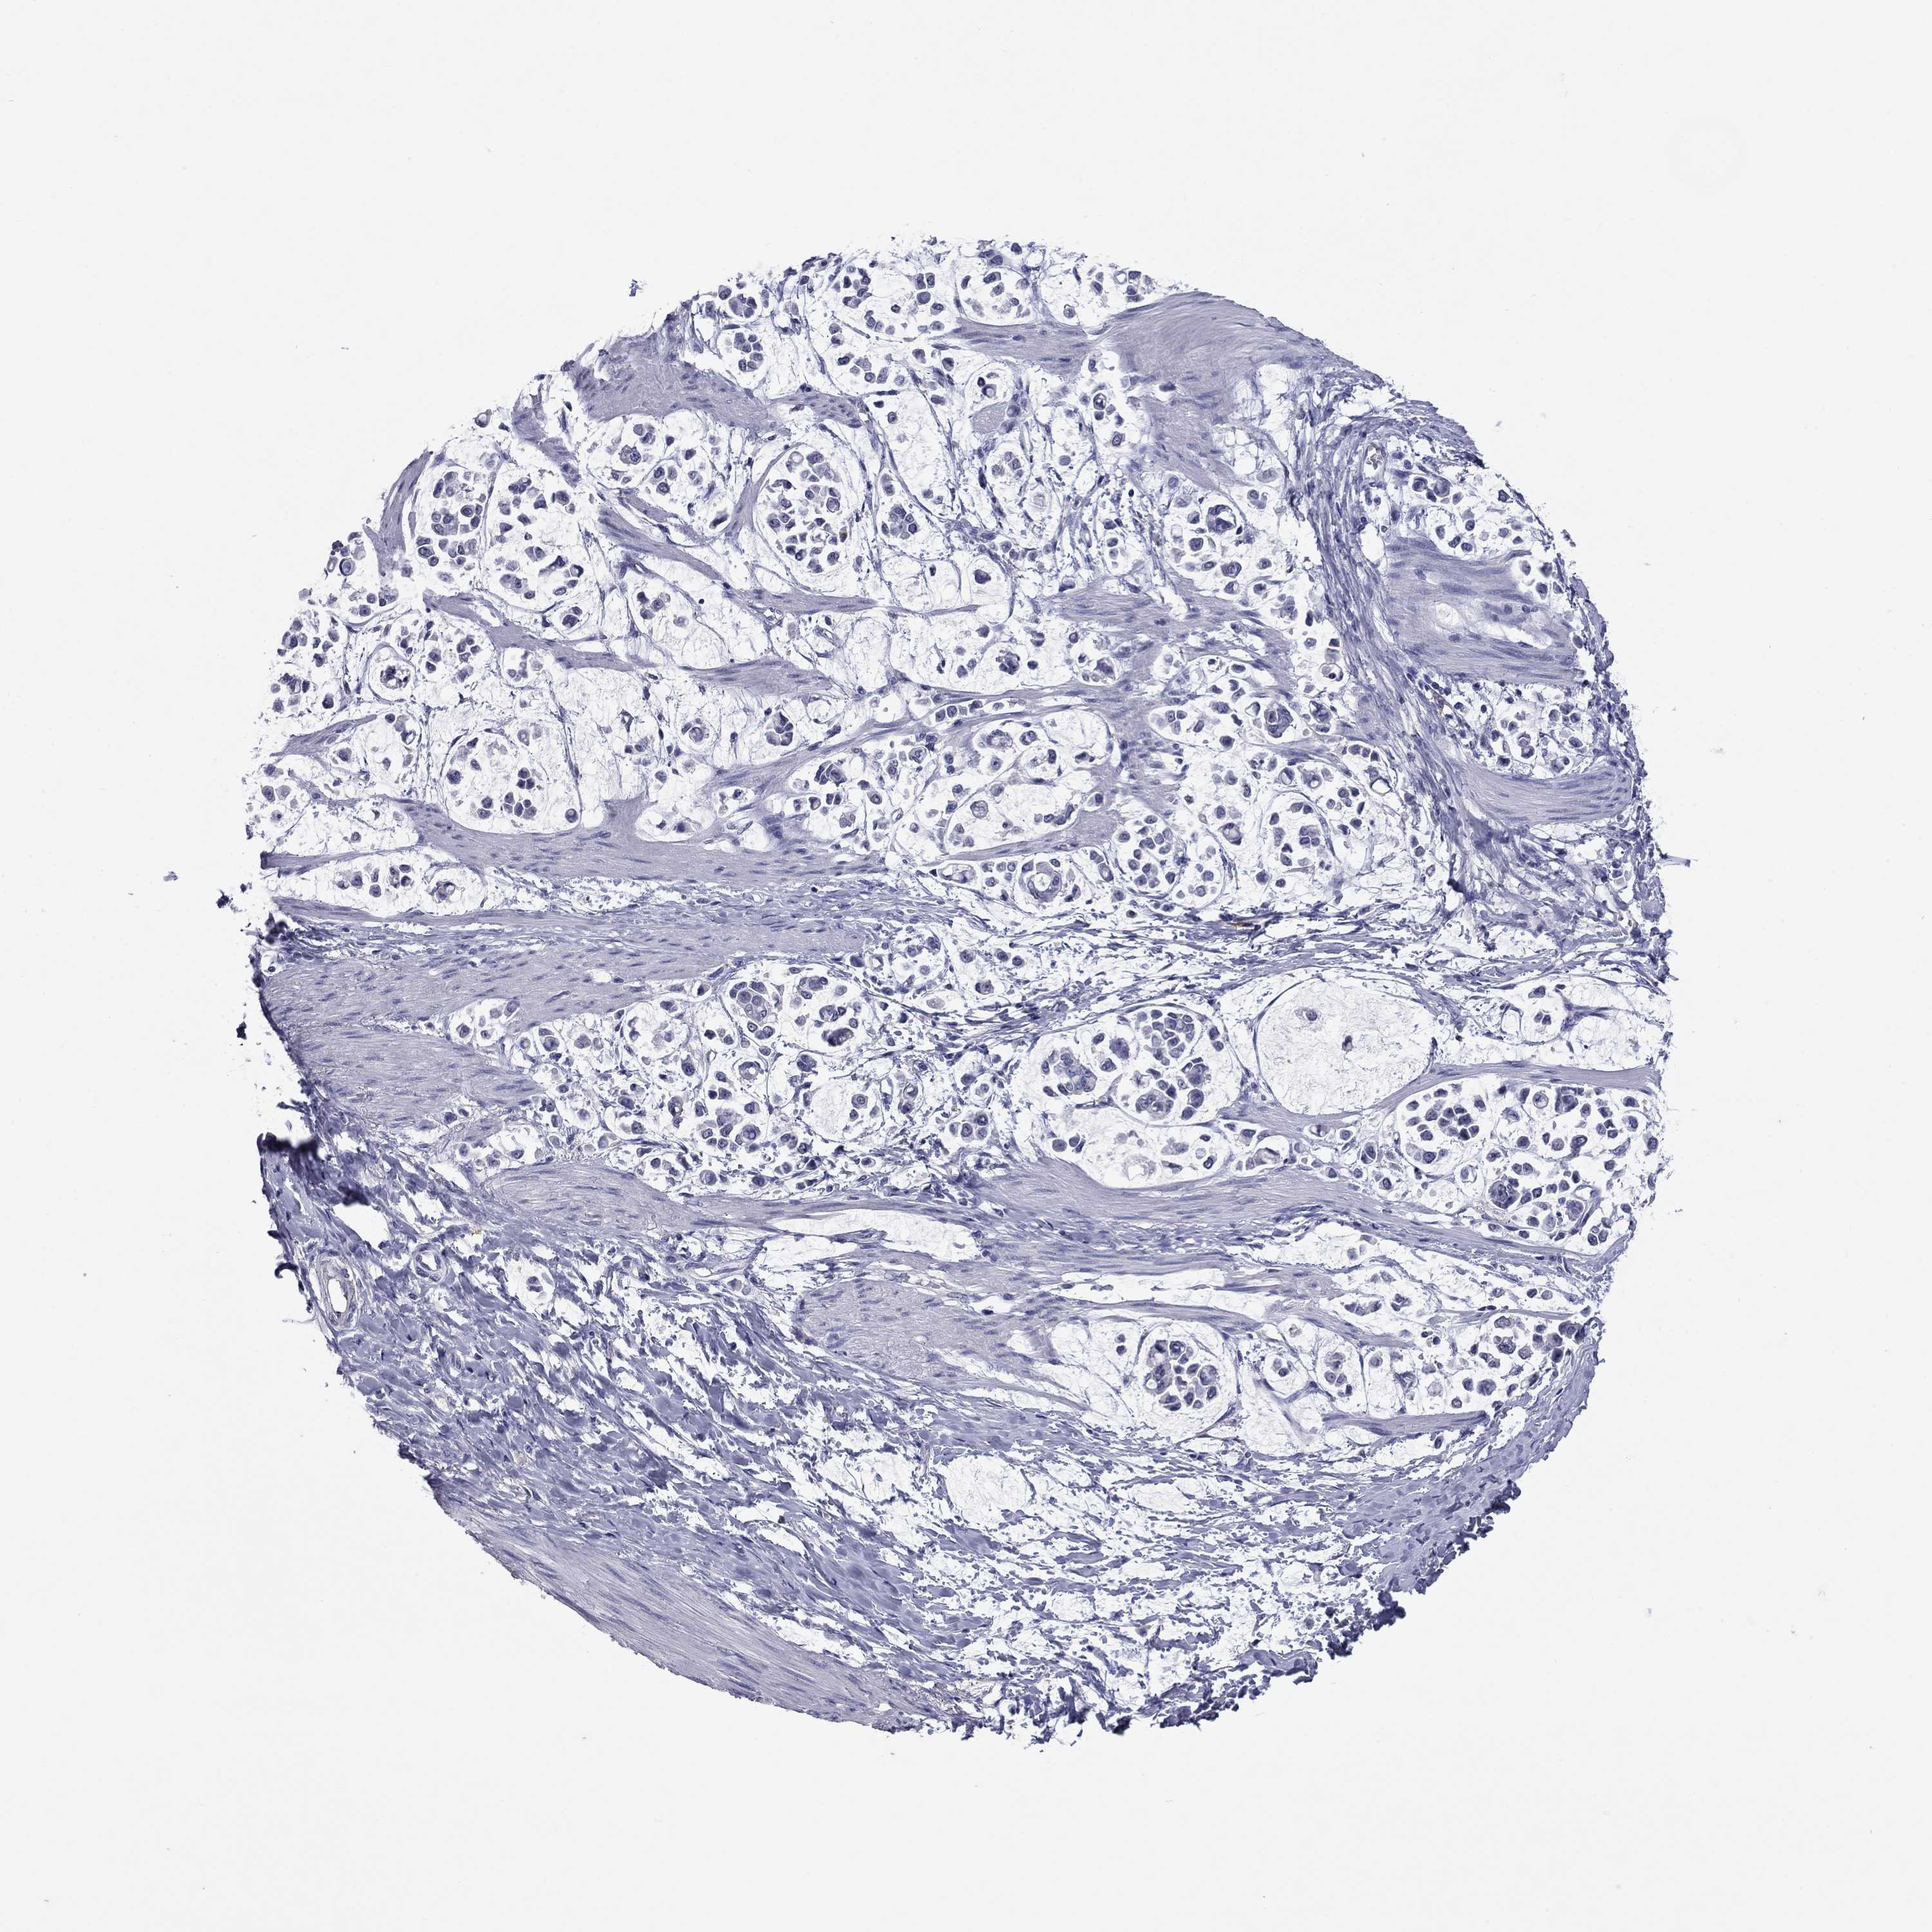

STOMACH CANCER - Protein expressioni

A mouse-over function shows sample information and annotation data. Click on an image to view it in a full screen mode. Samples can be filtered based on level of antibody staining by selecting one or several of the following categories: high, medium, low and not detected. The assay and annotation is described here.

Note that samples used for immunohistochemistry by the Human Protein Atlas do not correspond to samples in the TCGA dataset.

Antibody stainingi

Antibody staining in the annotated cell types in the current human tissue is reported as not detected, low, medium, or high, based on conventional immunohistochemistry profiling in selected tissues. This score is based on the combination of the staining intensity and fraction of stained cells.

Each image is clickable and will lead to virtual microscopy that enables deeper exploration of all samples and also displays staining intensity scores, fraction scores and subcellular localization as well as patient and tissue information for each sample.

Antibody HPA049552

Antibody HPA072442

Staining

High

Medium

Low

Not detected

Intensity

Strong

Moderate

Weak

Negative

Quantity

>75%

75%-25%

<25%

None

Location

Nuclear

Cytoplasmic/membranous

Cytoplasmic/membranous,nuclear

Adenocarcinoma, NOS

Adenocarcinoma, High grade